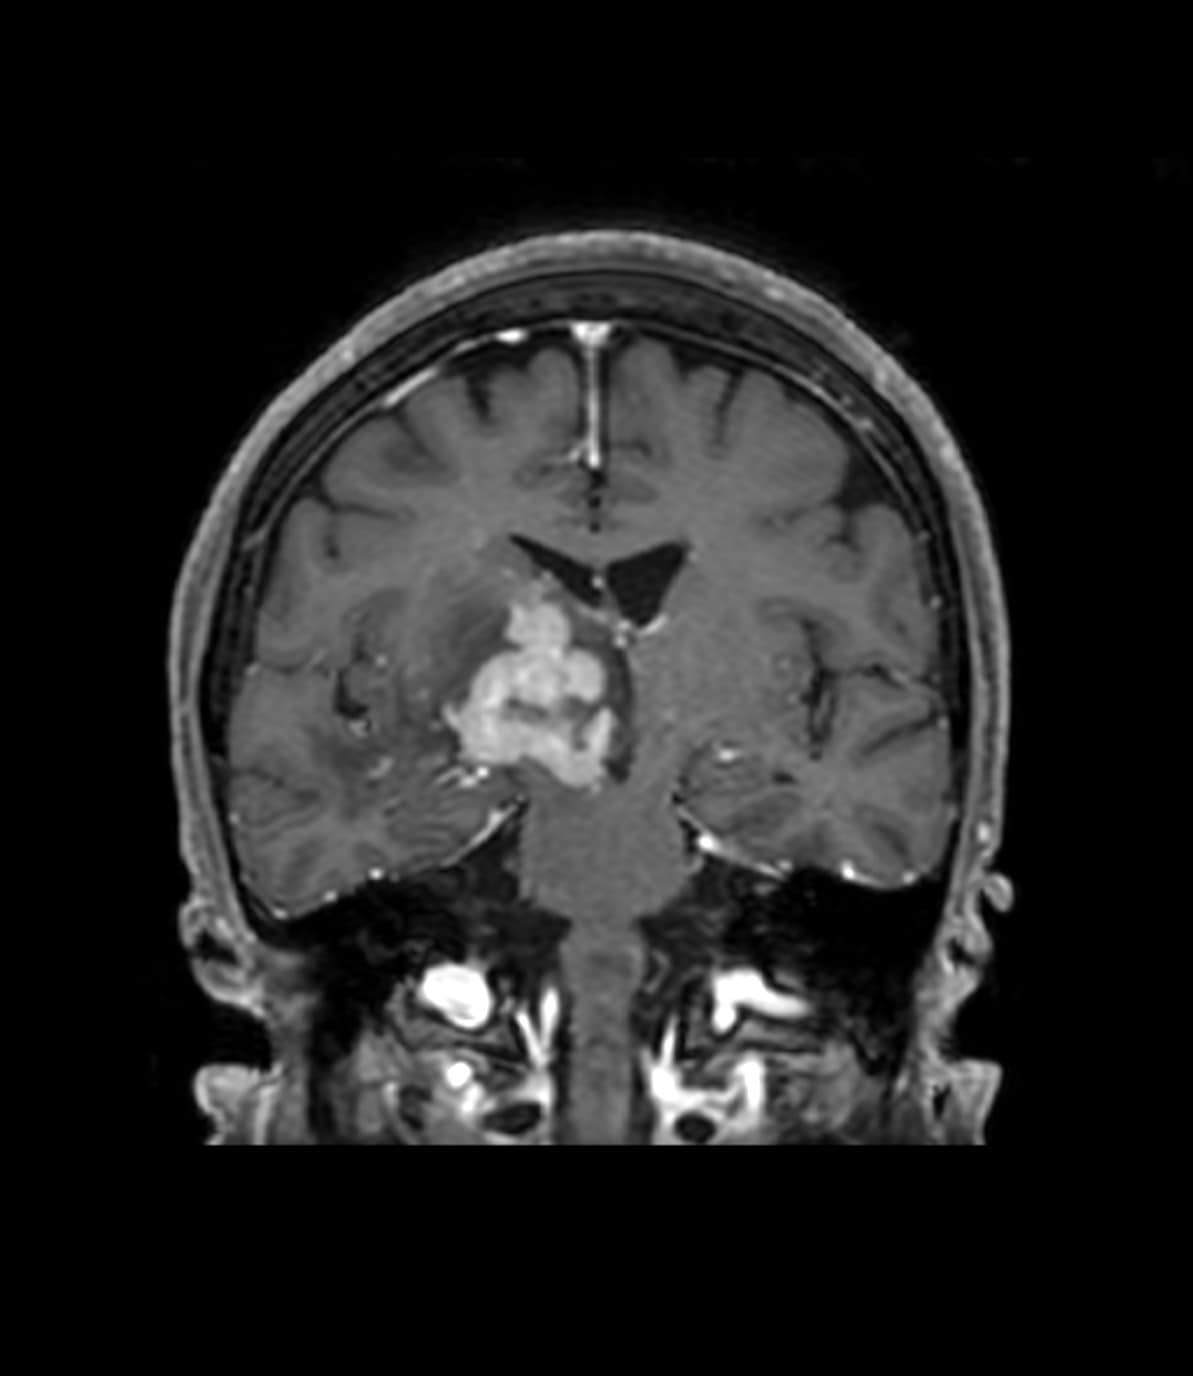

右基底核~視床~右中脳腹側にかけて均一で強いリング状増強効果を呈する腫瘤を認める。周囲に浮腫と思われるFLAIR 高信号域を認める。主病変の濃染部分はFLAIR等信号、DWI 高信号、ADCmap 低信号を呈している。MRS(TE=144)でChoが上昇、CrとNAAが低下している。ASLでは血流の顕著な上昇は認めない。中枢神経原発悪性リンパ腫(PCNSL)が疑われた。脳腫瘍生検の結果、中枢神経原発悪性リンパ腫(PCNSL)と診断された。

造影MRIにより腫瘍の範囲を正確に確認でき、腫瘍生検を行う際に病変を的確に捉えることができるようになると思われる。本症例のように浮腫を伴う脳腫瘍の場合、単純MRIのみでは浮腫と腫瘍の境界が不明瞭であり、腫瘍の範囲を把握するために造影MRIが必要と思われる。